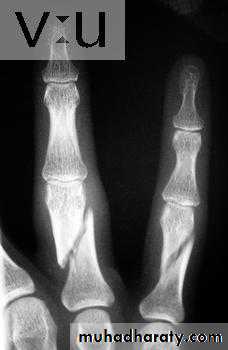

41Physeal injuries

10% of fractures in children

Salter - Harris classification:

1: separation of the epiphysis usually thru the calcified zone

2: separation of epiphysis & triangular piece of metaphysis

Wahby Ghalib

42

3: intra-articular # thru epiphysis then thru physis

4: intra-articular # thru epiphysis, physis, & metaphysis5: crushing of physis arrested growth

44# may not be visible initially

Types 1 & 2 : good Px except around the kneeTypes 3 & 4: need perfect reduction & f/u for re-displacement